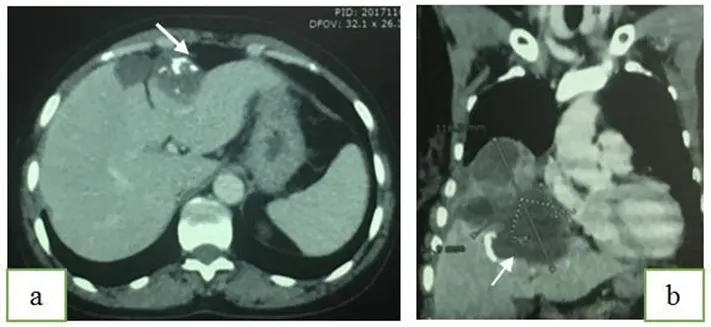

Observation 4Mr. M.G, aged 48, chronic smoker, with no other particular pathological history who complained for 2 months of a cough with purulent sputum, chest pain and dyspnea. The clinical examination had found a mixed effusion syndrome of the right hemithorax and a decline in the general condition. The chest X-ray had shown a right hydro-aeric image and the thoracic CT could not specify the pleural or parenchymal seat of this image (Fig-5). The bronchoscopy was normal.

Fig-5: Chest x-ray and chest scanner showing a right hydro-aeric image.